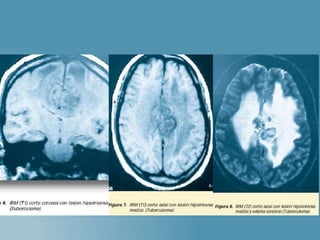

 Exudado en aracnoides provoca

severos trastornos visuales.

 Invaginación del bacilo en arterias

penetrantes = Encefalitis

(Prolifera en el parénquima)

 Vasculitis produce

isquemia/Necrosis en tallo cerebral

(CONFUNDEN CON TUMOR)

 Granulomas: en cerebro, cerebelo,

tallo.

 Zonas desmielinizadas

perivasculares